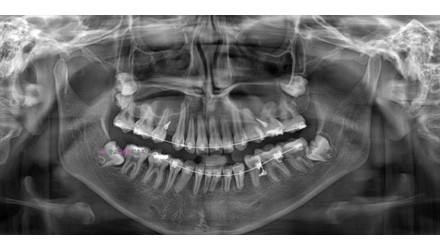

심*복 임플란트 시술 사례

전체 임플란트

2024.12.05

치료 전

2025.05.30

치료 후